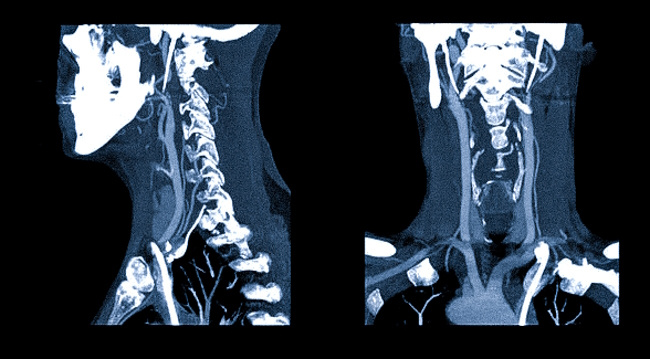

Спиральная компьютерная томография (СКТ) шеи — это высокоточный метод лучевой диагностики, который позволяет получить послойные изображения мягких тканей, лимфатических узлов, сосудов, позвоночных структур и органов данной области. Исследование помогает выявить патологические изменения даже на ранних стадиях и уточнить диагноз в сложных клинических случаях. Назначение СКТ всегда основывается на жалобах пациента, данных осмотра и результатах других обследований. Одним из частых показаний к проведению СКТ являются выраженные боли в области шеи, особенно если они сопровождаются ограничением подвижности, онемением рук или головными болями. Исследование позволяет выявить дегенеративные изменения шейного отдела позвоночника, костные разрастания, смещения позвонков, последствия травм и другие структурные нарушения. В случаях, когда рентгенография не даёт достаточной информации, СКТ помогает получить более детальную картину. СКТ шеи назначается при травмах, полученных в результате падений, до

Спиральная компьютерная томография (СКТ) шеи — это высокоточный метод лучевой диагностики, который позволяет получить послойные изображения мягких тканей, лимфатических узлов, сосудов, позвоночных структур и органов данной области. Исследование помогает выявить патологические изменения даже на ранних стадиях и уточнить диагноз в сложных клинических случаях. Назначение СКТ всегда основывается на жалобах пациента, данных осмотра и результатах других обследований.

При подозрении на патологии сосудов шеи — аневризмы, сужения, тромбозы — проводится СКТ с контрастированием. Контрастное вещество позволяет чётко визуализировать сосудистое русло и выявить нарушения кровотока. Такое исследование часто назначают при головокружениях, эпизодах потери сознания и других симптомах, связанных с возможным нарушением мозгового кровоснабжения.